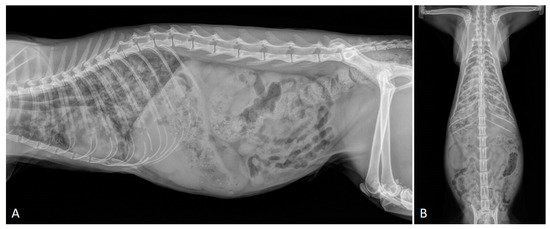

2.2. Radiographic Findings

- Crisi, P.E.; Aste, G.; Traversa, D.; Di Cesare, A.; Febo, E.; Vignoli, M.; Santori, D.; Luciani, A.; Boari, A. Single and mixed feline lungworm infections: Clinical, radiographic and therapeutic features of 26 cases (2013-2015). J. Feline Med. Surg. 2017, 19, 1017–1029. [Google Scholar] [CrossRef] [PubMed]

- Febo, E.; Crisi, P.E.; Traversa, D.; Luciani, A.; Di Tommaso, M.; Pantaleo, S.; Santori, D.; Di Cesare, A.; Boari, A.; Terragni, R.; et al. Comparison of clinical and imaging findings in cats with single and mixed lungworm infection. J. Feline Med. Surg. 2019, 21, 581–589. [Google Scholar] [CrossRef]

- Genchi, M.; Ferrari, N.; Fonti, P.; De Francesco, I.; Piazza, C.; Viglietti, A. Relation between Aelurostrongylus abstrusus larvae excretion, respiratory and radiographic signs in naturally infected cats. Vet. Parasitol. 2014, 206, 182–187. [Google Scholar] [CrossRef]

- Lacava, G.; Zini, E.; Marchesotti, F.; Domenech, O.; Romano, F.; Manzocchi, S.; Venco, L.; Auriemma, E. Computed tomography, radiology and echocardiography in cats naturally infected with Aelurostrongylus abstrusus. J. Feline Med. Surg. 2017, 19, 446–453. [Google Scholar] [CrossRef]

- Dennler, M.; Bass, D.A.; Gutierrez-Crespo, B.; Schnyder, M.; Guscetti, F.; Di Cesare, A.; Deplazes, P.; Kircher, P.R.; Glaus, T.M. Thoracic computed tomography, angiographic computed tomography, and pathology findings in six cats experimentally infected with aelurostrongylus abstrusus. Vet. Radiol. Ultrasound 2013, 54, 459–469. [Google Scholar] [CrossRef]